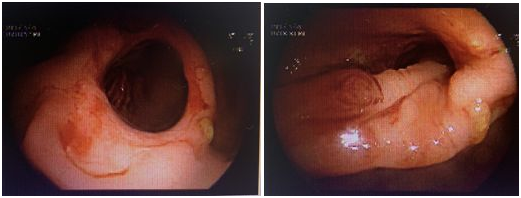

小腸鏡下看到環形潰爛

很快,消化內科曾志宇副主任醫師為小靜做了小腸鏡。經過四個小時的仔細探查,醫生髮現,小靜的小腸近端有多發息肉,遠端有環形潰瘍,潰瘍處伴有狹窄和局部畸形,考慮就是這個地方出血。病理結果顯示為胃粘膜異位,結合小靜的發病年齡,考慮病變為梅克爾憩室。梅克爾憩室是一種先天性消化道畸形,可以出現消化道出血、腸梗阻、憩室炎等,這就可以解釋為什麼小靜從1歲就開始反覆消化道出血了。